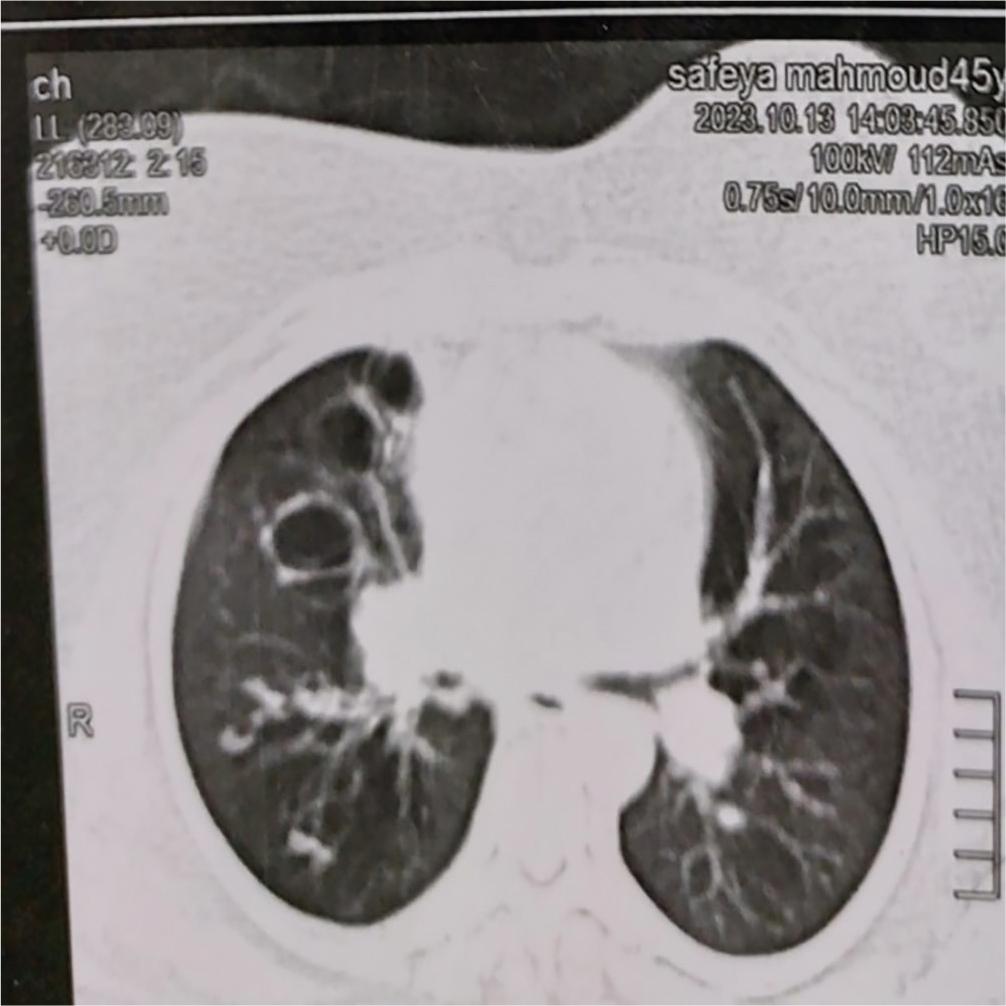

As regard the correlation between BSI score & FACED score and laboratory findings, we found that there was significant positive correlation between BSI & FACED scores and white blood cell count, ESR, and serum fibrinogen level (Table 3). Patients with bronchiectasis had a high plasma fibrinogen level, and the serum fibrinogen level was significantly increased with increasing severity of BSI & FACED scores (P-value = <0.001 for both) (Figures 2,3,4 and 5).

Cystic bronchiectasis.

Cylindrical bronchiectasis.